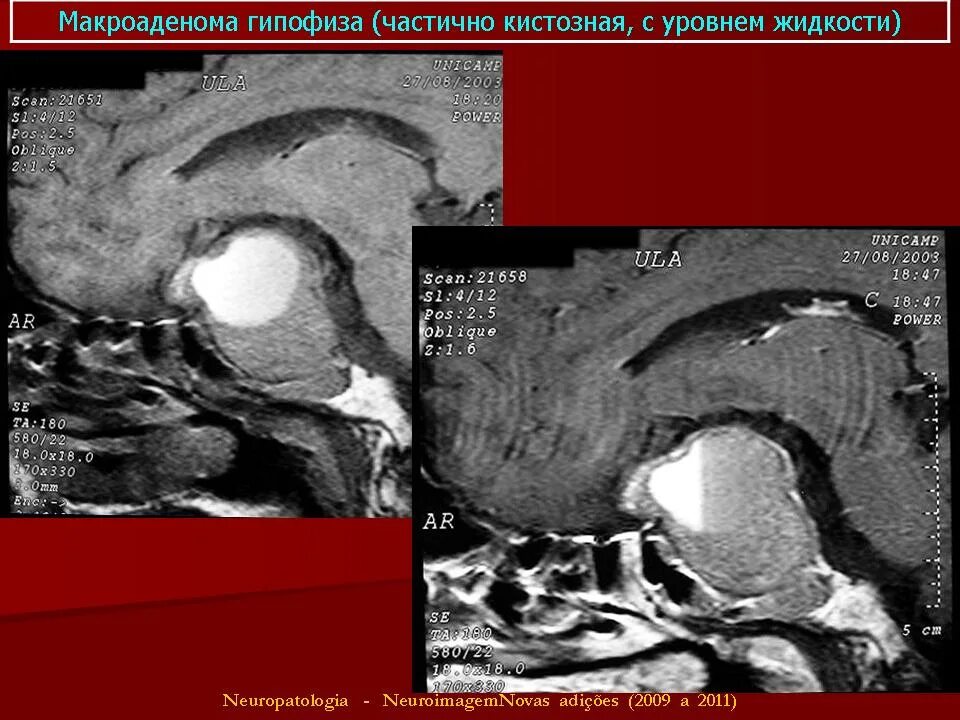

Макроаденома гипофиза